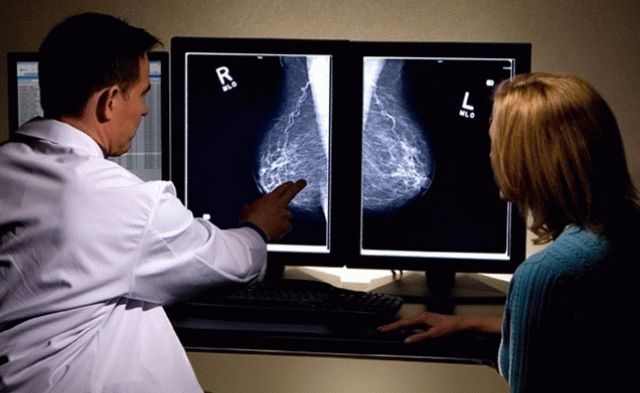

818МедицинаРак молочной железы: метастазы и лечение

Рак груди представляет собой злокачественное образование, которое формируется в клетках железистой ткани груди. Существует множество факторов, влияющих на появление данного заболевания. Значительную...